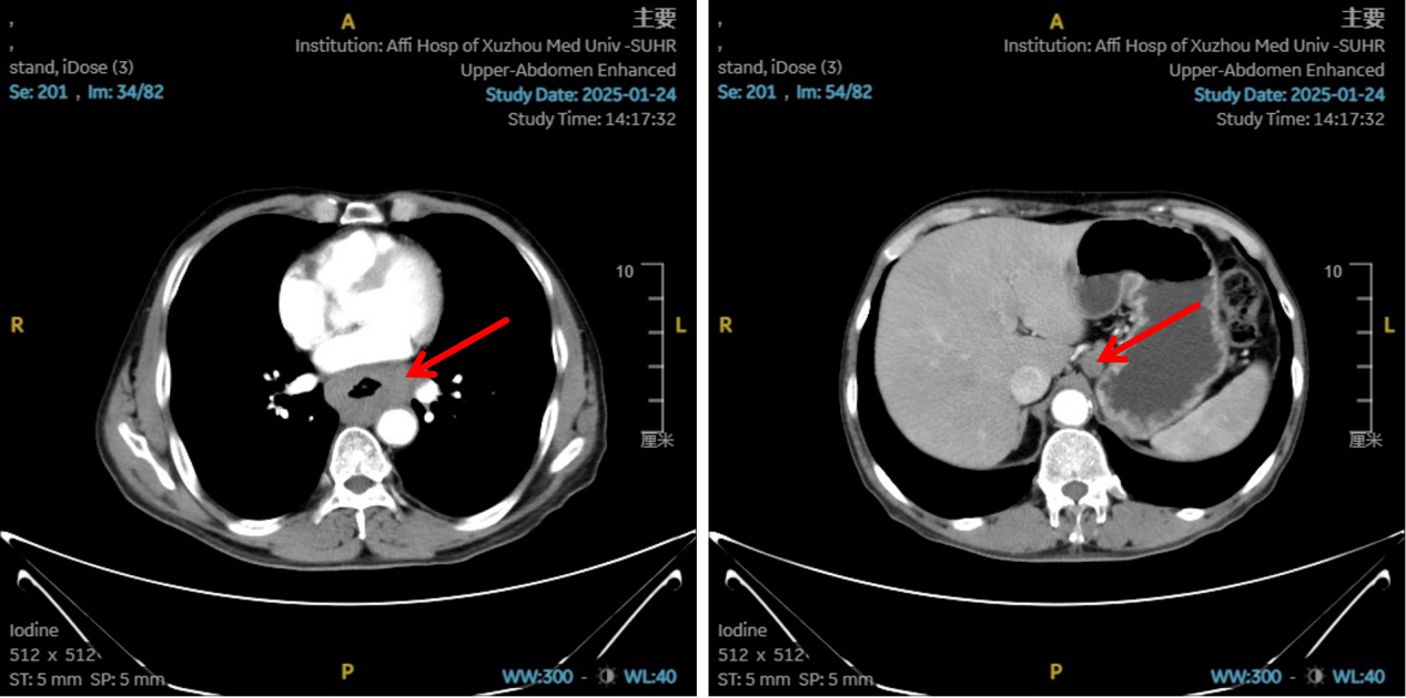

2025-01-22:患者行胃镜及病理检查确诊为食管鳞状细胞癌,CT提示病变位于胸中下段,伴纵隔、左肺门及胃小弯旁多发淋巴结转移,临床分期为cT4N2M0,属于局晚期食管癌。

图1:初治影像学 [图左:食管胸中下段管壁增厚,强化不均,较厚处管壁约17mm,边缘模糊,病灶局部与邻近大血管、气管壁分界不清。图右:纵隔内(3P、4、7)、左肺门及胃小弯旁示多发增大淋巴结影,部分融合,强化不均,较大者大小约18mm×15mm。]